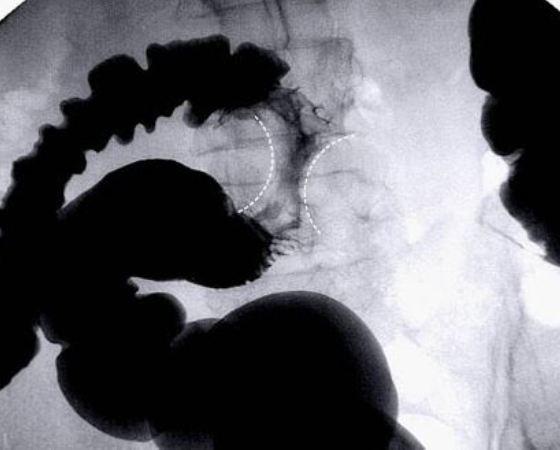

Ακτίνες Χ του παχέος εντέρου

Οι ακτίνες Χ του παχέος εντέρου γίνονται χρησιμοποιώντας τον βαριούχο υποκλυσμό, δηλαδή το γέμισμα του παχέος εντέρου με ένα λευκό υγρό που περιέχει σκιαγραφικό βάριο που επιτρέπει στον γιατρό να δει στο εσωτερικό του παχέος εντέρου και του ορθού και ανιχνεύει πολύποδες, όγκους και αλλαγές στον εντερικό ιστό. Οπως και στην εικονική κολονοσκόπηση, τυχόν ανωμαλίες που εμφανίζονται στις ακτίνες Χ, θα πρέπει να εξεταστούν με μια συμβατική κολονοσκόπηση.